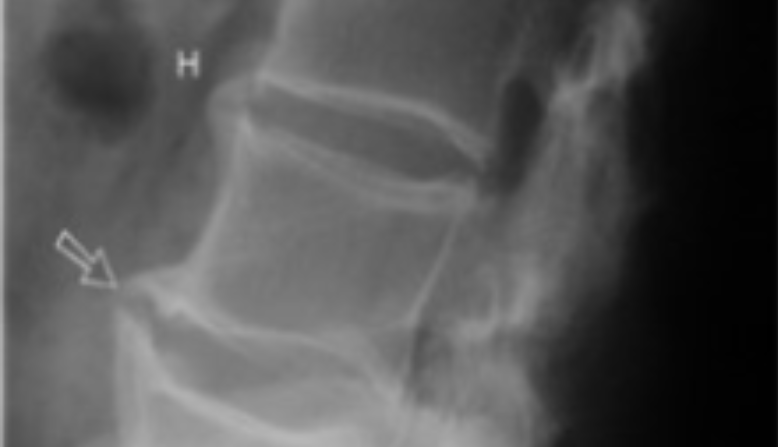

Spondylitis - a symptom of psoriatic arthritis

Spondylitis

• X-rays